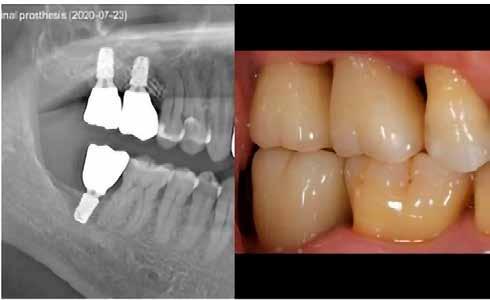

re készülő, átmenő csavarral rögzülő szólókoronák voltak. A felépítmény–implantátum aránya minden esetben meghaladta a 2:1-t. Vizsgáltuk az implantátumok túlélését, a crestalis csont felszívódását, illetve a transzmukozális elem hatását.

Jelen tanulmányban olyan eseteket mutatunk be, ahol a páciensek rövid és extra rövid implantátumokat (7,5 mm és 6,5 mm) kaptak, a végleges felépítmények transzmukozális fejek-

2. ábra: A transzmukozális fejek magassága az implantátumok átmérőjének és hosszának függvényében.

3. ábra: A vizsgálatban részt vevő koronák hossza az őket viselő implantátumok függvényében.